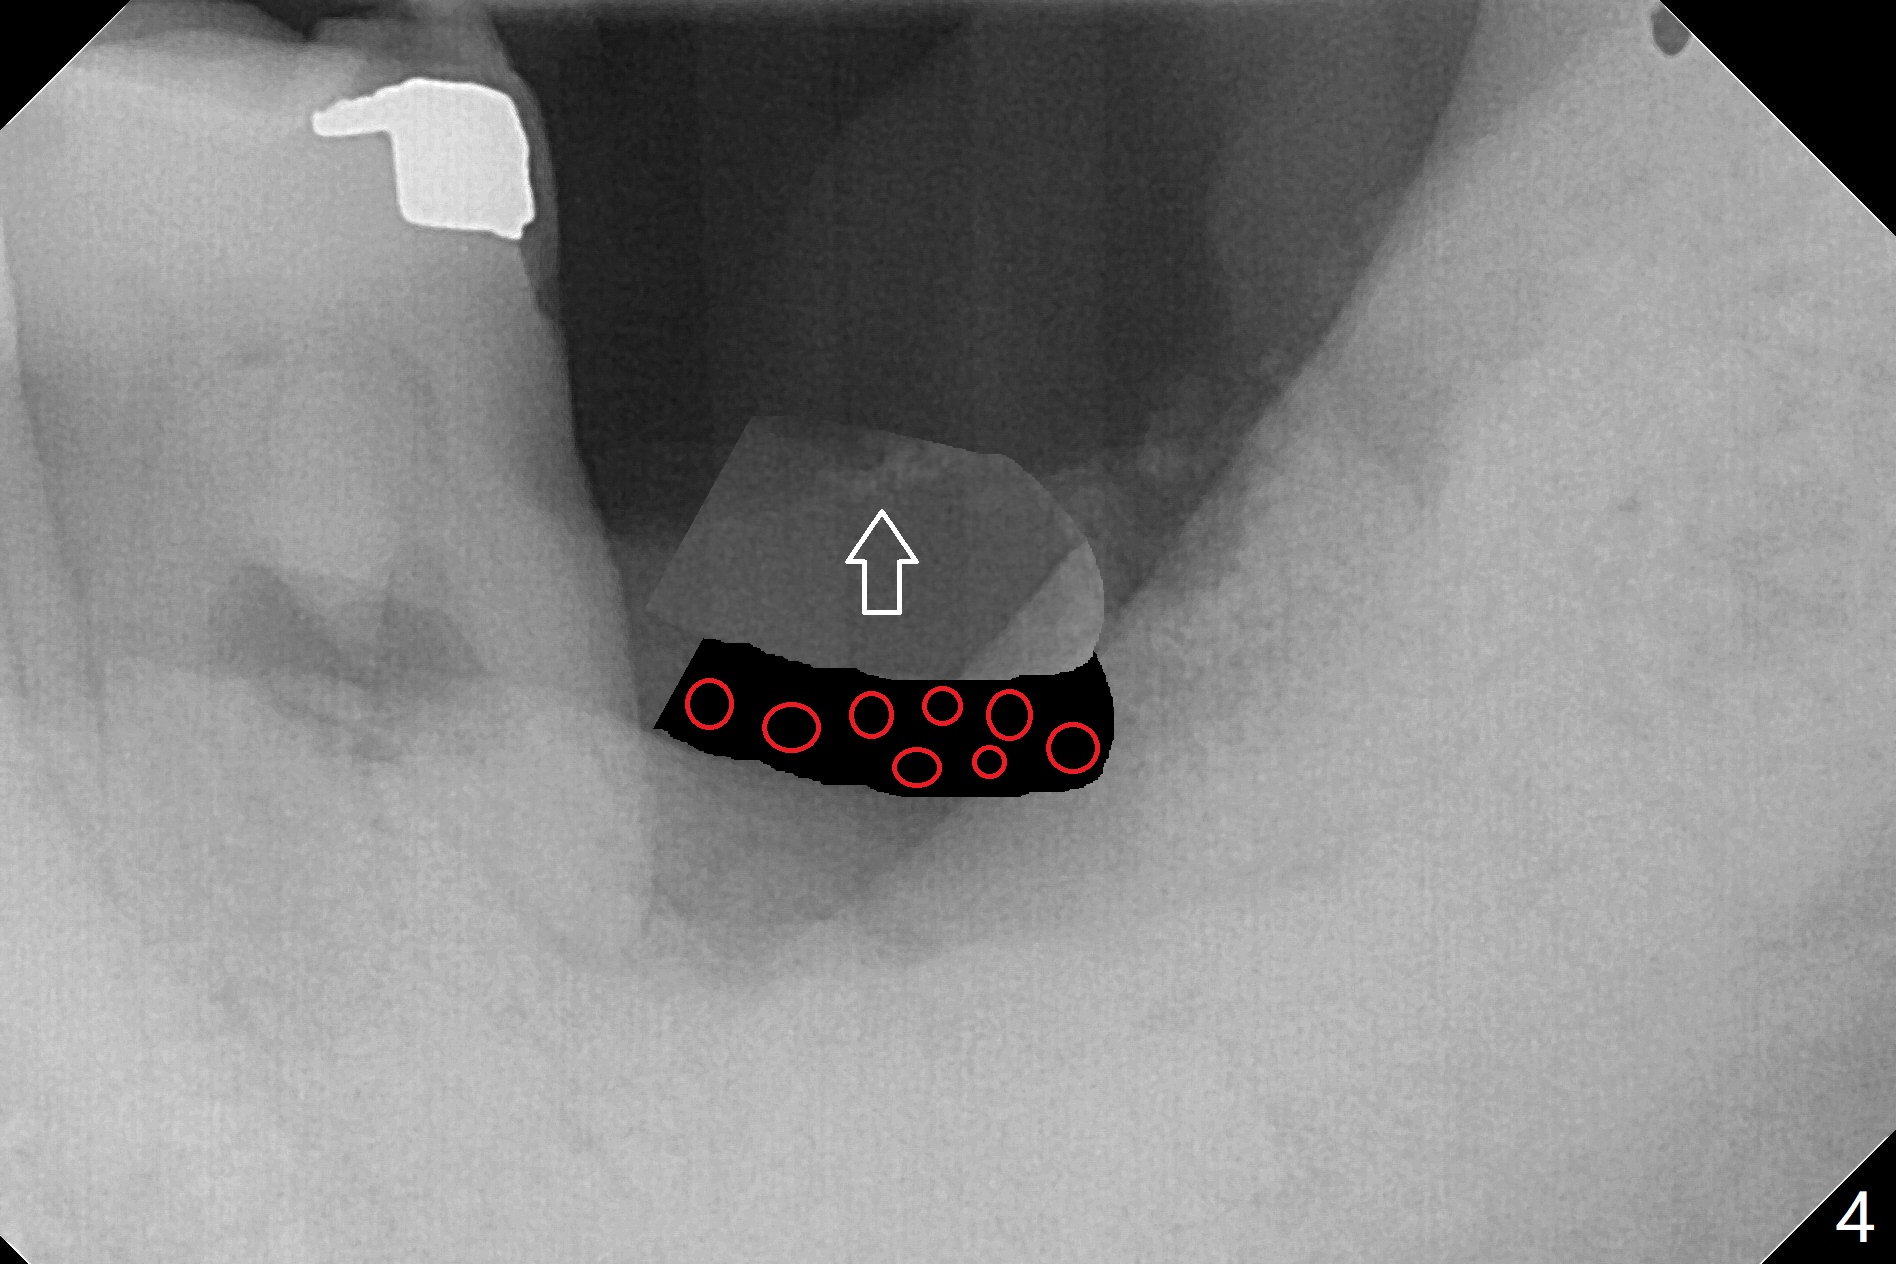

50岁男两年前不肯拔除左下7(图一),现在主动要求治疗(图二),需要做位点保留?怎么做的好?怎么收拾不动脑筋的惨剧(图三:仅远中牙槽窝植骨)?其实需要掀开近中粘骨膜(图四:箭头),然后植骨(红圆圈)。术后4.5个月近中缺损(图五:*),需要植牙植入很低(图六),离邻牙CEJ(<)很远。因此植体应该植入浅些(图七(CT矢状切面):箭头),离牙龈3毫米。放置袖3毫米(图八:粉红色)基台(紫色),然后在基台和植牙浅部植入粘性骨粉(图九:红圆圈)以及PRF膜(蓝线)。从冠状切面来看,颊侧(图十:B)需要多植骨,植牙前翻瓣(图十一:箭头),放置基台后(图十二),放置骨粉,膜,缝合。No Deviation 14 手术 Xin Wei, DDS, PhD, MS 1st edition 09/22/2020, last revision 03/02/2021